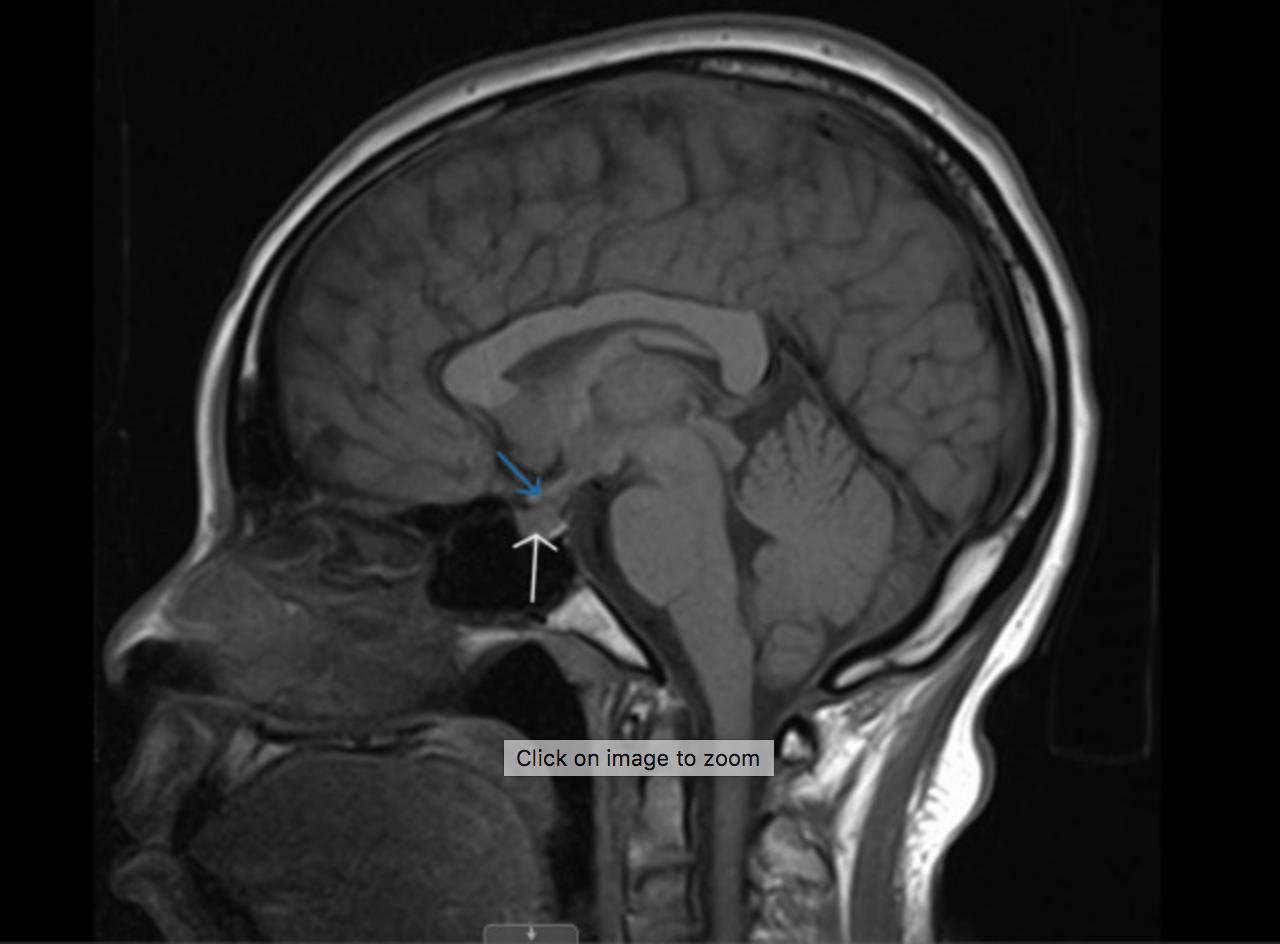

图1 脑mri,矢状切面.白色箭头:垂体;蓝色箭头:垂体柄